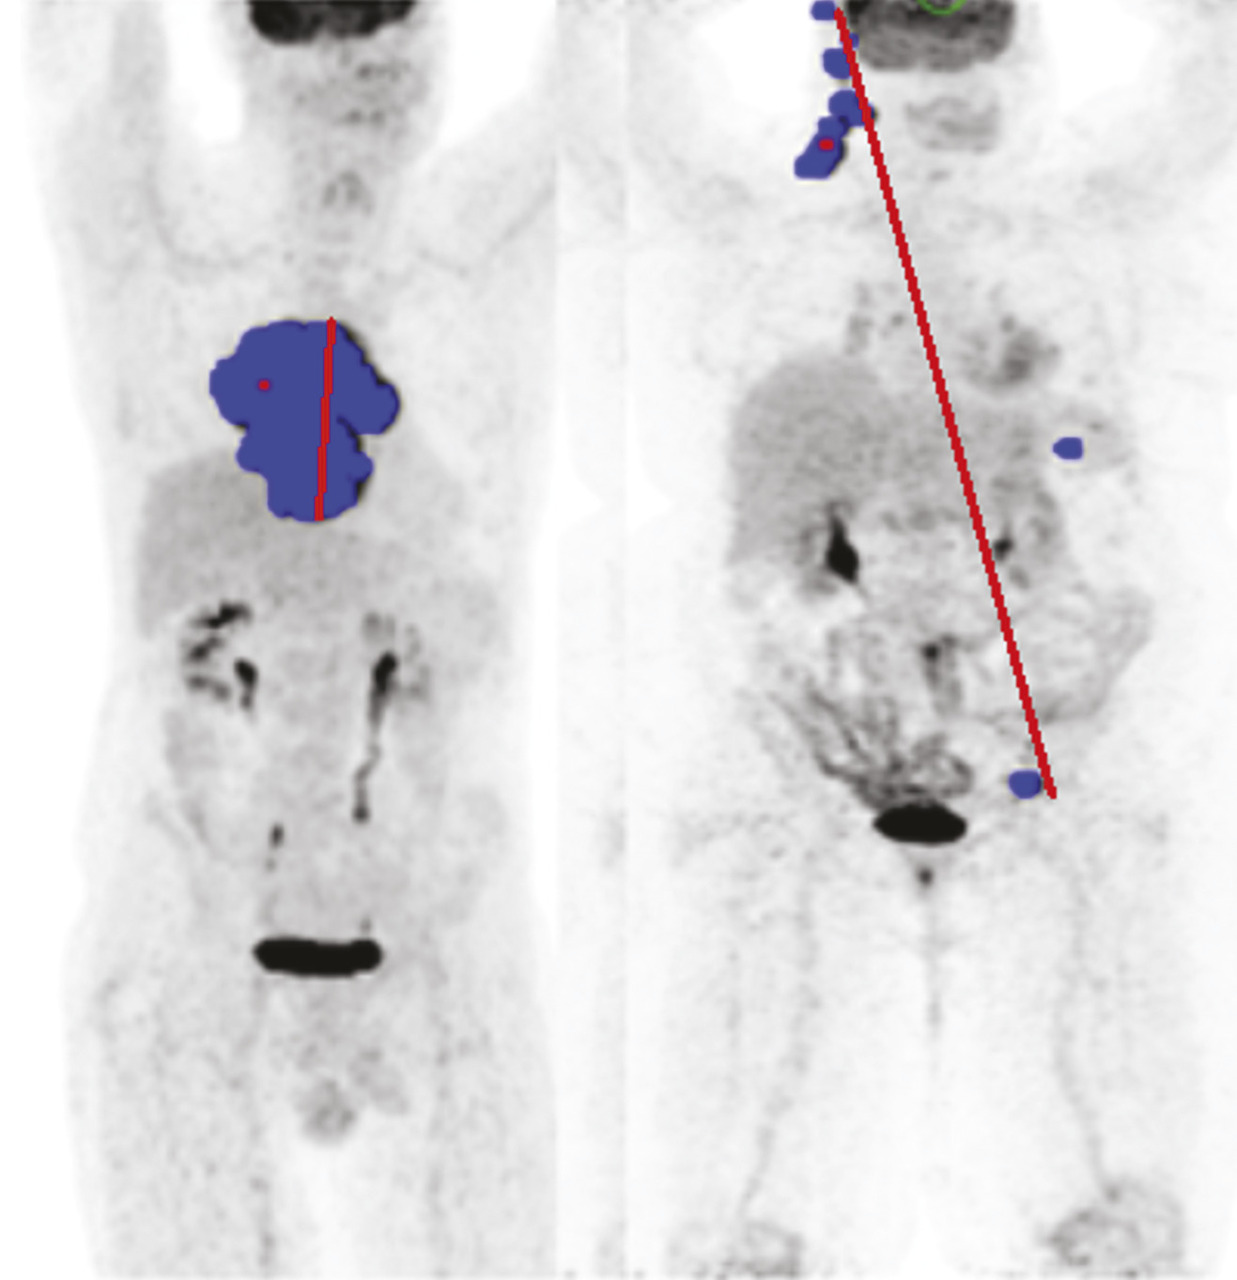

Plus récemment, la mesure de la dispersion des lésions, toujours sur le TEP initial, a été proposée comme facteur pronostique indépendant, en plus du TMTV et de la réponse à deux cycles. Ce nouvel indice appelé Dmax (distance maximale) mesure la distance entre les deux atteintes les plus éloignées. Ce paramètre est, dans l’esprit, une version quantifiée du stade d’Ann Arbor et constitue un indice pronostique additionnel pouvant être extrait des TEP de baseline (fig. 3 ).10

Plus généralement, ces nouveaux paramètres, appelés radiomics, sont des descripteurs quantifiés de la maladie et vont probablement constituer les futurs apports de la TEP pour identifier plus finement les groupes pronostiques de patients et construire des protocoles de traitement de plus en plus personnalisés.